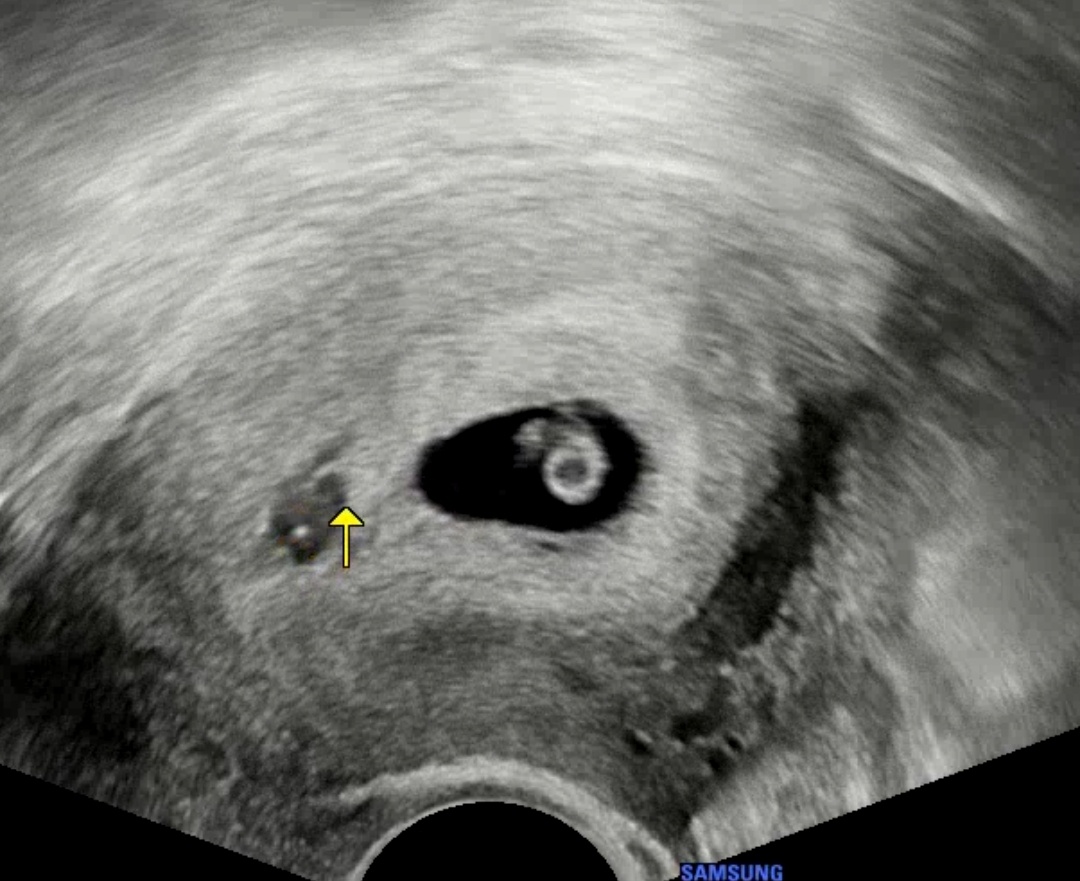

병원 점심시간에 도착했는데 선생님이 배려해 주셔서 바로 초음파를 봤다.

아기집 옆에 작게 피고임처럼 보이긴 하는데 흐려서 피고임이라고 확정은 지을 수 없다고 하셨다.

이 시기엔 아기가 자궁을 더 파고들면서 집을 확장시키기 때문에 조금 나오는 거였을 수도 있다고 하시면서

아기 3일 전에 봤는데 딱 3일만큼 잘 커있고 아기 심장도 쿵쾅쿵쾅 잘 뛰니까 걱정 말라고 해주셨다.. 휴..

선생님께서 불안하면 타이유라고 내막 유지시켜 주는 주사 맞고 가겠냐고 물어봐주셔서 맞고 왔다.ㅎㅎ